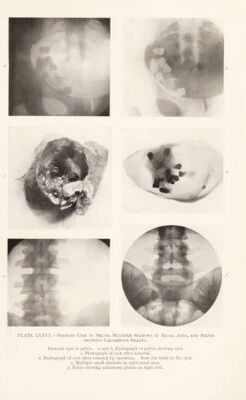

Radiography and radio-therapeutics / by Robert Knox.

510/544 page 384